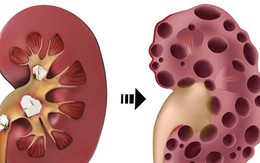

Thận có thể bị tàn phá ngay cả khi bạn không biết: Có 1 trong 11 dấu hiệu sau cần đến gặp bác sĩ ngay

13/11/2020 10:37

Theo Web MD, bệnh thận nếu không được điều trị, thận có thể ngừng hoạt động. Điều này rất nghiêm trọng và có thể nguy hiểm đến tính mạng.